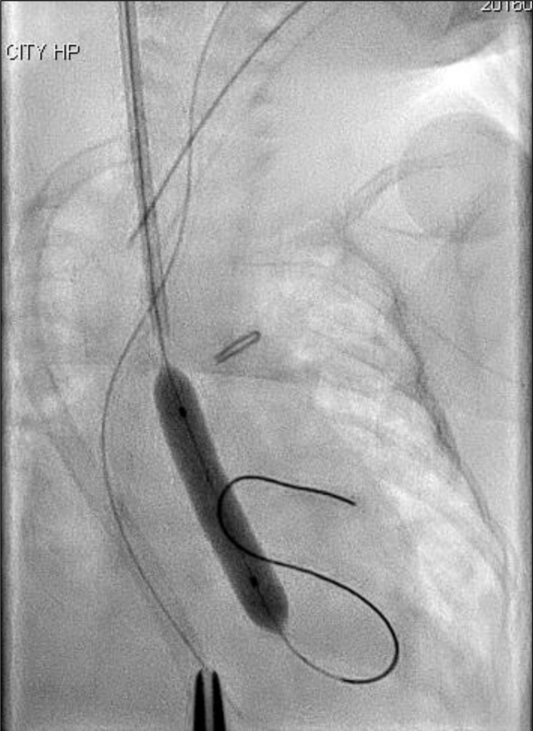

A silkworm-gut was tied on the sheath 25 mm from the tip of the sheath to prevent deep insertion, a semicircular incision was made on the common carotid artery, and a 4 Fr sheath (Terumo, Tokyo, Japan) was inserted. A 3 Fr SIM multipurpose 45° catheter (Fukuda, Tokyo, Japan) was passed through the sheath and introduced. An ascending aortography revealed an aortic valve diameter of 4.9 mm. A 4 × 20 mm TMP-Ped balloon catheter (Tokai Medical Products, Aichi, Japan) with the advantage of a short shoulder length was chosen. A 0.014′-inch Chikai guidewire (Fukuda, Tokyo, Japan) was maneuvered into the left ventricle, and the balloon catheter was positioned across the aortic valve and hand inflated immediately (Fig 2). The pressure of the ascending aorta was 55/30 mmHg, and the pull-back pressure gradient between the left ventricle and aorta was 22 mmHg. The haemodynamic condition improved significantly, and the body edema disappeared soon after this procedure. Echocardiography performed 2 days later showed no aortic valve insufficiency and a good left ventricle ejection fraction of 75%, and ultrasonography image demonstrated that there was no thrombus formation inside the right common carotid artery.

Figure 2. Balloon aortic valvuloplasty using a 4 × 20 mm TMP-Ped balloon catheter.